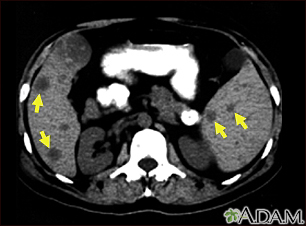

Spleen and liver metastases – CT scan

This CT scan of the upper abdomen shows multiple tumors in the liver and spleen that have spread (metastasized) from an original intestinal cancer (carcinoma).